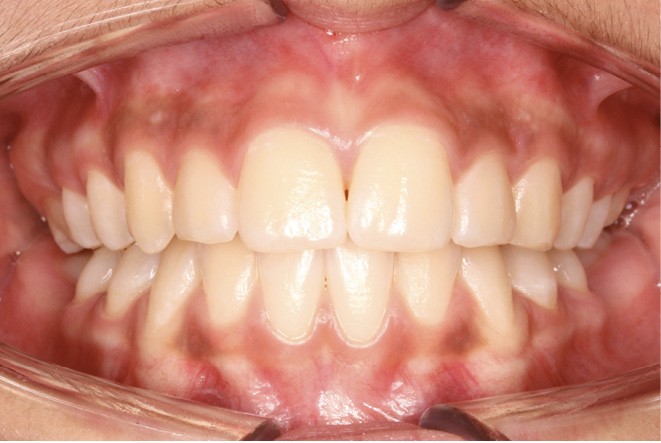

Examen endobuccal (fig. 2a-e)

L’hygiène est satisfaisante et le parodonte sain. On note aux deux arcades l’absence des premières molaires et la fermeture partielle des espaces d’extraction avec mésiorotation marquée de 17, 27 et 37. À la mandibule, l’encombrement antérieur est estimé à 2 mm et les espaces d’extraction résiduels à 12 mm.

Dans le sens transversal, malgré une occlusion correcte des secteurs latéraux, on observe une endoalvéolie maxillaire et une non-concordance des médianes incisives avec déviation de la médiane mandibulaire vers la droite. Le recouvrement incisif est normal.